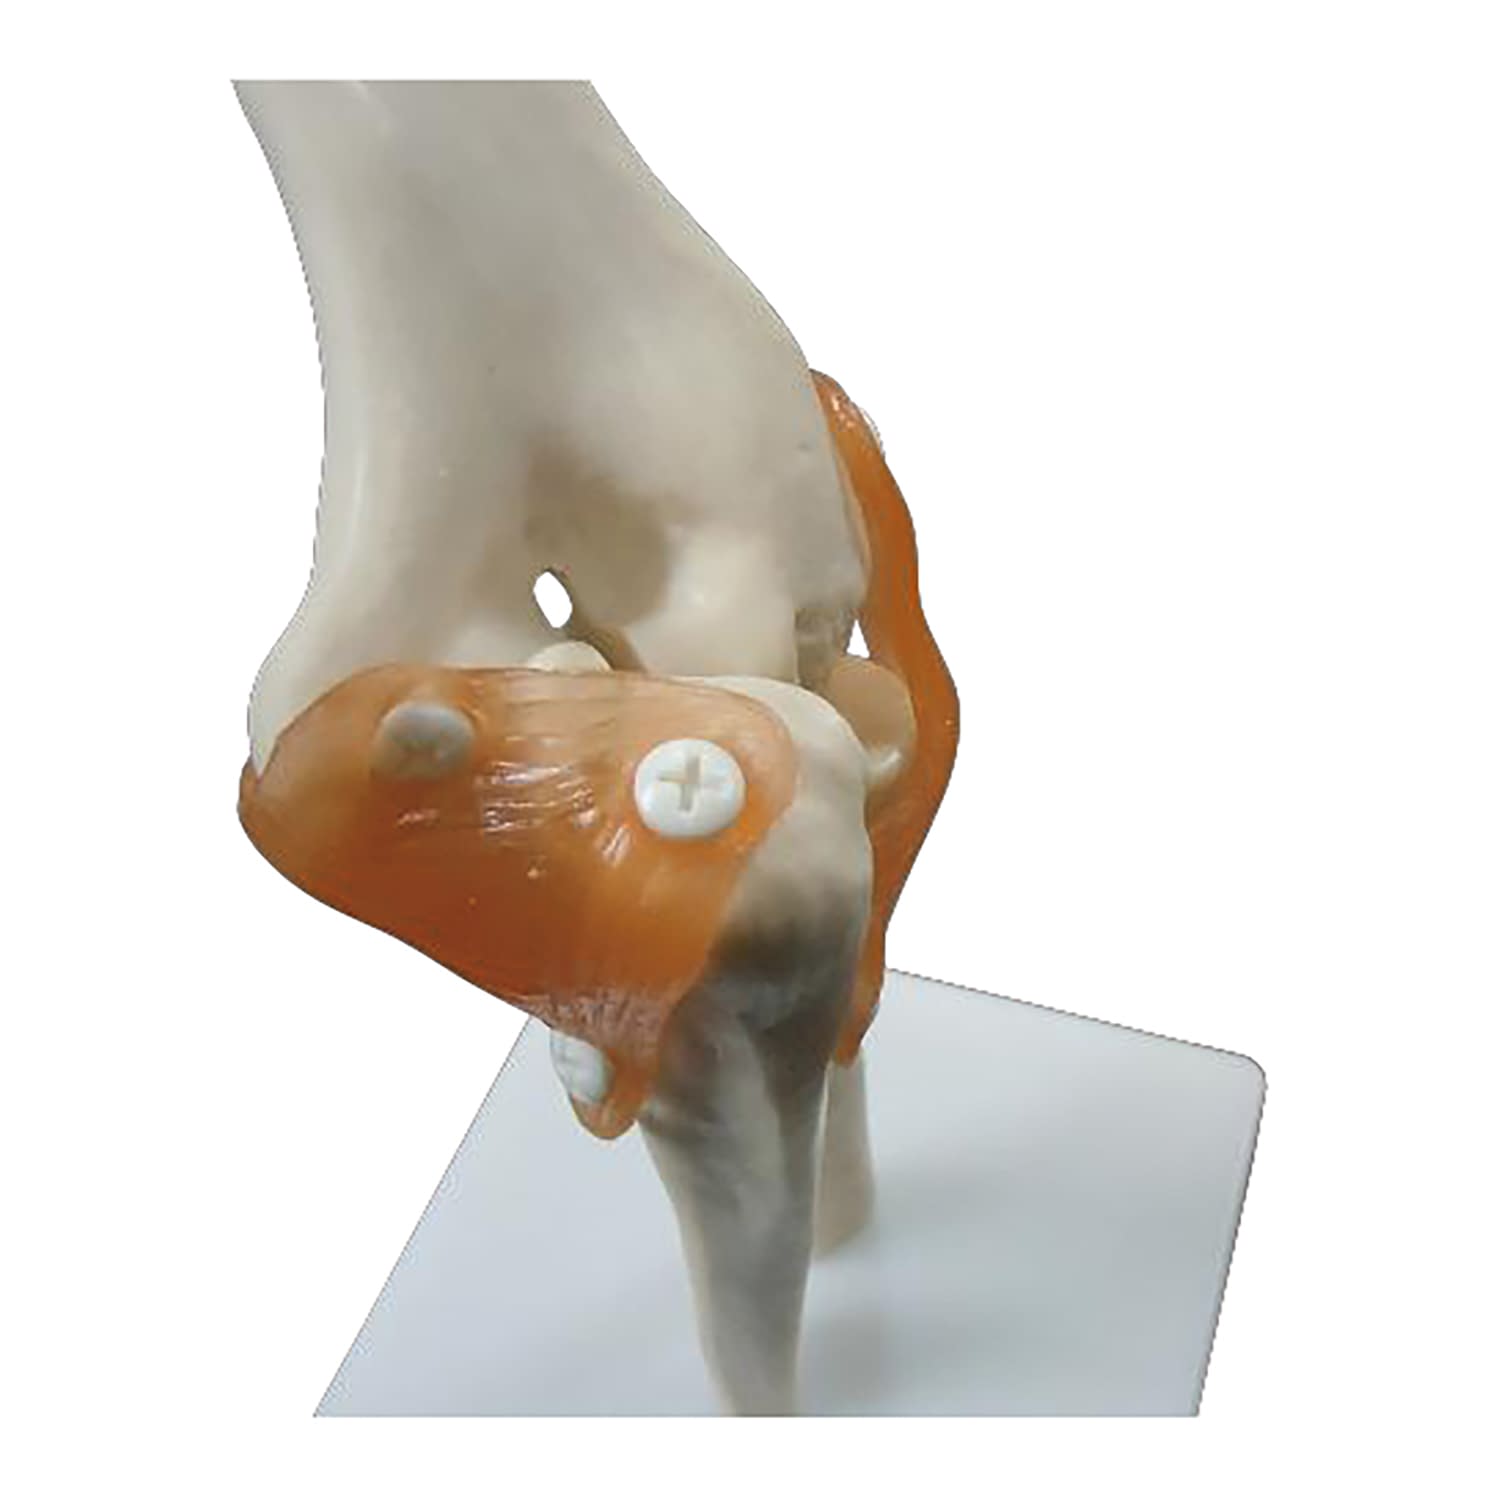

『実物大 靭帯付き肘模型 教材模型 25-5557-00 大阪人体模型センター|マツヨシ【松吉医科器械】医療・介護用品の総合サイト』はセカイモンで60916aeaf70cから出品され、207の入札を集めて05月12日 21時 21分に、7680円で落札されました。即決価格は7680円でした。決済方法はに対応。岐阜県からの発送料は落札者が負担しました。PRオプションはストア、取りナビ(ベータ版)を利用したオークション、即買でした。

実物大 靭帯付き肘模型 教材模型 25-5557-00 大阪人体模型センター|マツヨシ【松吉医科器械】医療・介護用品の総合サイト,Amazon.co.jp: 関節 模型,The original Lazer ZX-S as featured in Kyosho's Japanese 1997 Kyosho Catalog. Interestingly, there's no mention of the LA-121 Yokomo wheel adaptor, and the ZX-S is seen here with ZX-R 2.2 wheels.,The original Lazer ZX-S as featured in Kyosho's Japanese 1997 Kyosho Catalog. Interestingly, there's no mention of the LA-121 Yokomo wheel adaptor, and the ZX-S is seen here with ZX-R 2.2 wheels.,Proline Power PROTOform 1971 Chevrolet Camaro Z28 Clear Body VTA Class PRM155240 Car/Truck Bodies Wings & Decals